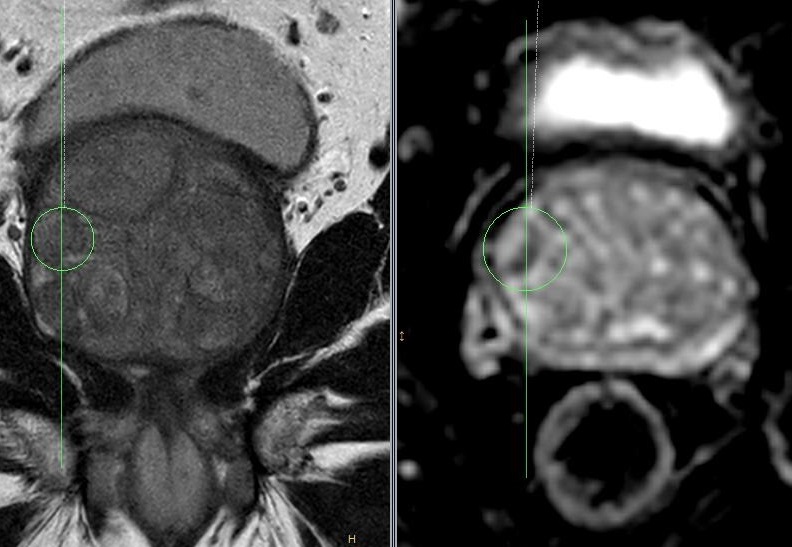

Dank dem vor der Prostatabiopsie durchgeführten multiparametischem MRT der Prostata kann die Präzision der Probenentnahme erhöht werden. Dieses Verfahren wird als Fusionsbiopsie bezeichnet.

System zur Fusionsbiopsie der Prostata_Urologie_Amriswil  mpMRT Prostata mit MRT Fusionsvorbereitung_Urologie_Amriswil Probenentnahme-Schema der Fusionsbiopsie der Prostata_Urologie_Amriswil

Fusionsbiopsie-System zur präzisen Gewebeprobenentnahme aus der Prostata: mpMRT-Prostata mit Darstellung der Entnahmezonen ("biopsy plan & shot cores")